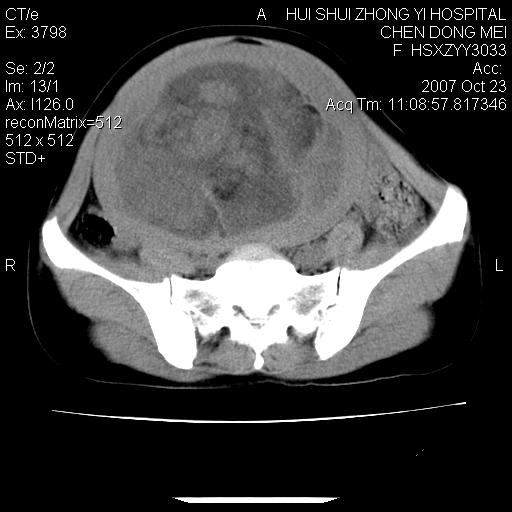

标题: CT10156:女.43岁,发现中下腹部包都块2年 [打印本页]

标题: CT10156:女.43岁,发现中下腹部包都块2年

发现中下腹部包都块2年。2年来月经不规律。

腹腔巨大软组织密度影,边缘光滑,包膜完整,内囊变坏死。腹膜后及盆腔内淋巴结肿大。结合病史考虑卵巢癌可能性大。

病变巨大,呈囊实性改变,包膜较厚且完整,内见分膈,周围脏器明显受压移位,病变与左侧附件关系密切,考虑来源左侧附件的囊腺瘤,不除外癌变可能;畸胎瘤可能性较小。

病变巨大,呈囊实性改变,包膜较厚且完整,内见分膈,周围脏器明显受压移位,病变与左侧附件关系密切,考虑来源左侧附件的囊腺瘤,盆腔内见肿大淋巴结,不除外癌变可能。

病变巨大,呈囊实性改变,包膜较厚且完整,内见分膈,周围脏器明显受压移位,病变与左侧附件关系密切,考虑来源左侧附件的囊腺瘤,不除外癌变可能